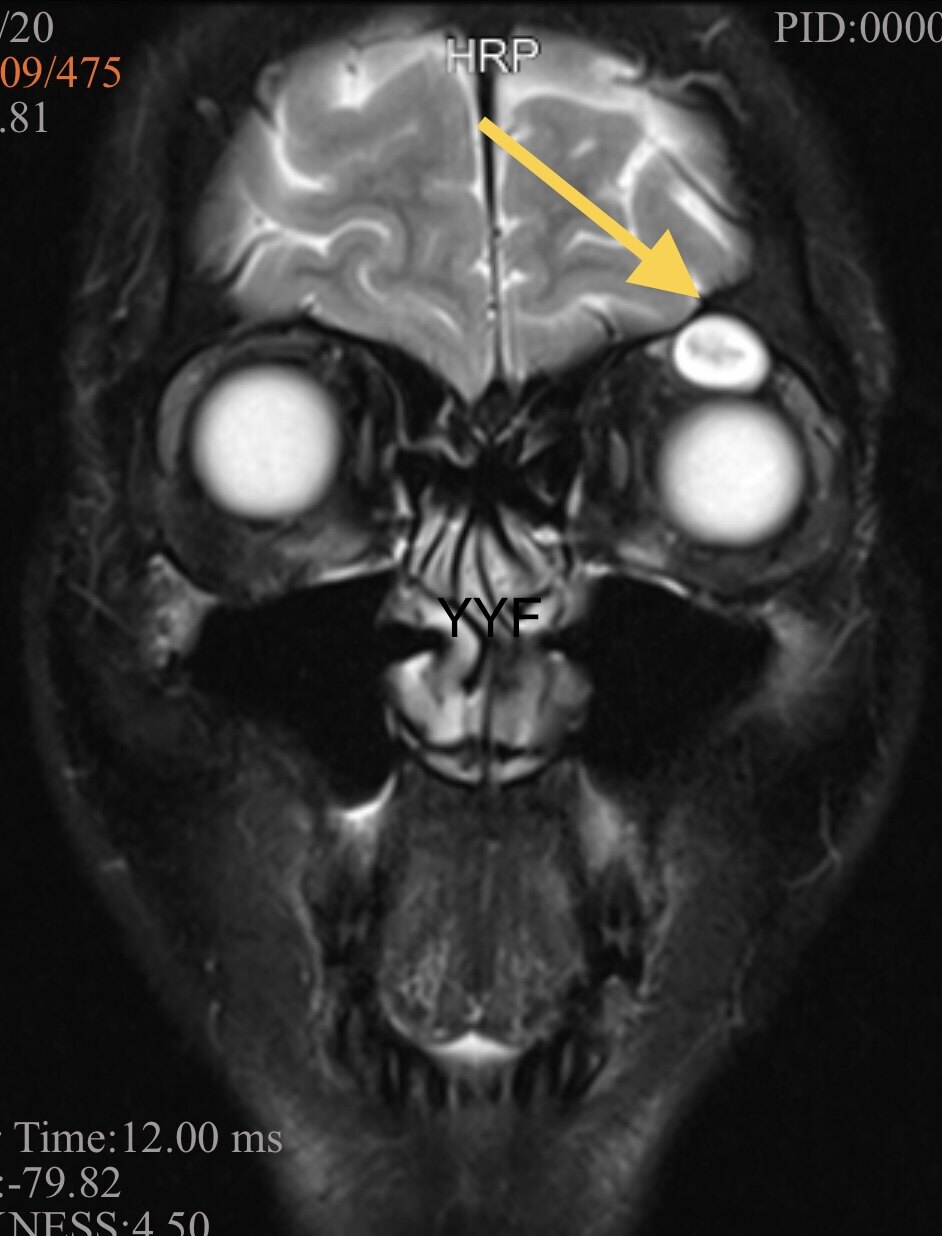

影像学显示肿物呈现不规则、结节状。

矢状位可以看到串珠样结节状外观及邻近结构的关系

T2加权表现有特征性

白色区域为病变起源的神经纤维